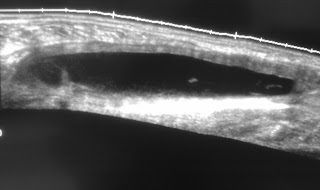

Intramuscular haematoma in the gastrocnemius